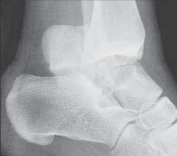

FIG 1 • Hawkins classification of talar fractures. A. Type I: disruption of anterolateral perfusion. B. Type II: medial perfusion intact. C. Type III: all D sources of blood flow injured. D. Type IV: dislocation of all articulations. 1. In the type III injury, the transverse fracture of the talar neck is associated with dislocation of the talar body. The incidence of osteonecrosis of the talar body is 50% to 100%. All major perfusion to the body of the talus is damaged ( FIG 1C). 2. A type IV injury of the talar neck has been documented; it is a type III fracture-dislocation with associated talonavicular dislocation.2 All extraosseous blood flow to the talus is considered disrupted. The value of the Hawkins classification is that it allows the orthopedic surgeon to predict what to expect with a specific talar neck injury. Open reduction and rigid internal fixation is the recommended treatment ( FIG 1D). 1. Talar body fractures are defined as fractures extending into or posterior to the lateral process. PATIENT HISTORY AND PHYSICAL FINDINGS 2. Fractures of the talus are commonly associated with vehicular trauma and falls. 1. The relationship of severe lower extremity trauma and airbags is well known. After airbag deployment, the torso and lower extremities are directed toward the floor panel of the car. 2. I believe that the incidence of high-energy hindfoot trauma will increase over time. Globally, transport related injuries remain the leading cause of disability from injury. By 2020, traffic injuries will increase from a current 9th position to 3rd disability-adjusted life years lost. 3. The history and the clinical status of the talar injury must be carefully recorded because the injury severity is likely to correlate with the long-term patient outcome. 1. On the initial examination the physician should note pain, motion, crepitus, deformity, soft tissue swelling, open fractures, and associated fractures of adjacent bones to the foot and ankle and should perform a complete neurovascular evaluation of the extremity. 4. Detailed documentation of the talus fracture pattern and local soft tissue injury is paramount. 1. Soft tissue local pressure phenomenon, commonly found anterolaterally in closed type III fractures of the talar neck, may precipitate full-thickness pressure necrosis of the skin if not decompressed early. 2. Severe swelling of the ankle is common in the acute fracture of the talus and may progress to fracture blister formation, precluding safe execution of operative incisions. 5. The physician should examine the skin for swelling, ecchy-mosis, fracture blisters, and deformity; these are signs of a closed fracture. 1. A closed injury with mild or moderate swelling (bony landmarks palpable) indicates talar neck type I and II fractures and process fractures. 2. A closed injury with severe swelling indicates talar neck type III and IV fractures and body fractures. 6. Open fractures will be apparent by the transverse, medial, or supramalleolar traumatic laceration of the ankle. Lateral, posterior, and plantar wounds are uncommon. 7. The physician should perform vascular, neurosensory, and myotendinous examinations of the foot and ankle. IMAGING AND OTHER DIAGNOSTIC STUDIES 8. Three plain radiographic views are necessary to radiographi-cally evaluate talus fractures: anteroposterior (AP), mortise (15-degree internal rotation view), and lateral images of the ankle. 1. The AP and mortise views of the ankle demonstrate alignment of the talar body in the ankle mortise. The lateral view depicts the sagittal outline of the talus. 9. The Canale view is used to assess varus or valgus malalignment of the talar neck, particularly with Hawkins type I and II injuries. The knee must be flexed and the foot in equinus and everted, with the x-ray tube directed 15 degrees caudad ( FIG 2A).

--- A B C ### FIG 2 • Radiology of talar fractures. A. Canale view showing medial and lateral talar neck provisionally reduced. B. Lateral process fracture less obvious on plain film. C. Lateral process fracture as shown on CT scan. 1. Because of the high-energy nature of fractures of the talus, AP and oblique views of the foot should be a standard addition to the three-view plain film ankle protocol so as not to miss associated midfoot and forefoot injuries ( FIG 2B). 2. Computed tomography (CT) provides important additional information to the three-view plain film series of the ankle. Thirty-degree coronal and paraxial CT imaging is important to confirm Hawkins type I fractures of the talar neck and plan treatment of talar body fractures with extension posterior to the lateral process. Reconstructions of both sagittal and coronal CT studies provide valuable information about incremental pathoanatomy of the entire talus, medial to lateral and anterior to posterior, respectively. In addition, confirmation of a process fracture that is not clearly viewed by plain film is easily diagnosed by CT ( FIG 2C). DIFFERENTIAL DIAGNOSIS 3. Process fracture of the talus 1. Lateral process fracture 2. Medial process fracture 4. Head of talus fracture 5. Neck of talus fracture 6. Body of talus fracture 7. Neck and body of talus fracture 8. Fracture-dislocation of talus 1. Involving body 2. Involving neck and body 9. Extruded talus (Any of these injuries to the talus may be open fractures, affecting management.) NONOPERATIVE MANAGEMENT 10. Fractures of the talus include a spectrum of injury patterns ranging from isolated regions of the talus (eg, lateral process) to severely comminuted talus fractures involving all parts of bone, making nonoperative management inappropriate. 1. High-energy injury mechanisms that cause talus fractures precipitate fracture displacement and joint surface incongruity. 2. Medial and lateral process fractures, minimally displaced (less than 2 mm) and involving less than 1 cm of bone, are commonly managed nonoperatively. 1. These injuries are treated acutely in well-padded, compressive dressings with posterior splints and non-weight bearing. Swelling and immediate pain in the ankle improve significantly by 7 to 10 days. The patient is subsequently converted to a short-leg non-weight-bearing cast for 6 weeks, followed by progressive range of ankle and subtalar motion and return to weight bearing in a removable fracture-boot. 2. If the process fracture is severely comminuted, precluding surgical reconstruction, the same initial and definitive nonoperative management is employed. 3. Isolated fractures of the head of the talus without dislocation and without displacement are largely stable fractures. These injuries require plain radiographic evaluation of both the ipsilateral foot and ankle to confirm the isolated nature of the injury. I recommend CT scanning (axial and transverse views of foot and ankle) of this injury to rule out associated midfoot pathology. 1. Acutely, an isolated, nondisplaced talar head fracture is splinted for 7 to 10 days with subsequent short-leg casting in neutral plantarflexion with non-weight bearing for 4 weeks. Intermittent daily ankle and subtalar motion with Achilles tendon stretching should follow with application of a removable fracture boot. The patient remains non-weight bearing until 6 to 8 weeks after injury. Next, progressive weight bearing, range of motion, stretching, and strengthening of the entire lower extremity are recommended. 4. The Hawkins type I fracture of the neck of the talus is a nondisplaced talar neck fracture. The talus remains anatomi-cally positioned in the ankle and subtalar joint with minimal potential for disruption of perfusion to the bone. 1. A subgroup of these injuries may present with displacement of the talar neck on initial injury plain radiographs. After closed manipulation of the fracture in plantarflexion, the talar neck fracture may reduce. A true Hawkins type I talar neck fracture will not displace even with gentle dorsiflexion. The type I fracture strongly warrants a CT scan, with sagittal reconstruction, to confirm anatomic alignment of the talar neck. 5. If there is displacement of the neck fracture, the injury must be reclassified as a type II, which requires surgical treatment to obtain, and maintain, the reduction. 1. Truly nondisplaced fractures of neck of the talus can be treated nonoperatively in a short-leg non-weight-bearing cast for 6 to 8 weeks. Close follow-up is recommended to watch for any displacement of the neck fracture. At 6 to 8 weeks after the injury, progressive weight bearing, range of motion, stretching, and strengthening are initiated. 10. Injury forces precipitating fractures of the dome of the talus are universally severe, causing articular displacement, and are an indication for surgery. Open fractures of the talus, even with no displacement, are best managed with rigid surgical stabilization to allow for wound care and early motion. SURGICAL MANAGEMENT 11. The timing of operative management of talus fractures has been an area of controversy, specifically whether the displaced talus fracture is an orthopedic emergency. 1. One recent study indicates that orthopedic trauma surgeons do not believe a displaced fracture of the neck of the talus is an orthopedic emergency. 2. However, it is important to differentiate the potential of vascular injury to the talar body from soft tissue and neurovascular compromise of the foot because of injury to the talus. In particular, fracture-dislocation of the body of the talus is associated with compromised blood flow to the bone, the threat of pressure phenomenon to the skin, and possible tibial nerve dysfunction. 3. The acute severity of soft tissue swelling or the impact of an open hindfoot wound may preclude safe, immediate reconstruction of the talus fracture after reduction of the dislocation. 12. Foot and ankle external fixation is a suitable treatment option, with staged definitive fixation applied accordingly. 1. Any open talus fracture must be treated as an orthopedic emergency. 2. Preoperative antibiotics may be selected on the basis of wound contamination. These include a cephalosporin and possibly gentamicin. Penicillin is added if gross or farm contamination is present. All patients should receive a tetanus toxoid booster. 3. The patient is taken to the operating room and after soft tissue débridement the wound receives at least 3 to 9 L of normal saline using pulsed lavage. 4. At this time, in addition to partial or complete fixation of the talus fracture, provisional foot and ankle external fixation may be used to provide soft tissue and osseous stabilization before delayed closure. 13. Regarding general guidelines for fractures of the body, neck, and head of talus fractures, surgical management is indicated with fracture displacement, malalignment, subluxation, dislocation, or instability. 1. Recent studies indicate that displacement or malalignment will have a negative impact on foot function. Two millimeters of fracture displacement has been shown to affect subtalar joint mechanics. 2. There is less agreement regarding surgical indications for process fractures of the talus. Acute, displaced fractures with large fragments showing extension into the subtalar joint by CT imaging are best treated with open reduction and internal fixation. 14. A displaced fracture of the neck of the talus is one of the most common indications for surgery on the talus. The fracture is known to start, in the coronal plane, along the medial neck and extend laterally until completion. 1. There are two common types of neck fractures: an extra-articular pattern and an intra-articular type that extends into the subtalar joint. 1. The displaced extra-articular vertical neck fracture is routinely amenable to closed reduction by applying dorsal-to-plantar pressure on the head of the talus associated with longitudinal traction and plantarflexion of the forefoot. Immediate reduction of this fracture diminishes concerns for soft tissue, neurovascular, and osseous compromise. 2. The intra-articular pattern is less likely to cooperate with closed manipulation owing to the obliquity of the fracture as it extends posterior into the subtalar joint. This fracture pattern is more deserving of immediate or early surgery. 15. For patients with severe open fractures of the talus, or closed injuries in which soft tissue compromise precludes immediate open management, temporizing external fixation may be effective. 1. The goals of temporary external fixation are to maintain the length of the talus for reconstruction, facilitate soft tissue management, and restore general alignment. External fixation is rarely definitive management for talus fractures. 2. Displaced, open or closed, fractures benefit most from rigid internal fixation for bone healing and early motion. However, a recent report evaluating results of the extruded talus identified definitive external fixation as an option to manage the purely dislocated talus. This is an excellent treatment option to stabilize the ankle and subtalar and talonavicular articulations of the talus. Preoperative Planning 16. Operative planning for talus fractures requires evaluation of imaging studies to clearly understand the relationships of all major fracture fragments. 1. A preoperative CT scan of the fracture is standard when confronted with a comminuted talar neck or body fracture. The surgeon must become familiar with the morphology of the bone and its many contours to facilitate reconstruction. 17. Intraoperative visibility and access to talar fragments are routinely challenging, but these variables can be largely facilitated by correct patient positioning, surgical approaches, adequate operating room lighting (headlamp), attention to reduction techniques, and implants selected. All play a key role in preoperative planning. 18. The principles of open treatment are restoring articular con-gruity, maximizing the revascularization potential of the bone, and allowing early motion of the ankle and subtalar joints. 19. The use of a radiolucent table and a headlamp promotes optimal visualization. 20. A tray of fine-tipped, sharp and strong bone elevators, dental probes, Freer elevators, small bone clamps, mini/small lamina spreaders, and small distractors or external fixation equipment is routinely needed not only for talus fracture fixation but also all fine articular fracture reconstructions. 1. Small interfragmentary (3.5 mm) cortical screw fixation and mini-fragment (2.7 or 2.0 mm) screw/plate instrumentation is commonly needed for talus fracture fixation. 1. An extra-long mini-screw (2.7 or 2.0 mm) inventory is recommended, with screws up to 60 mm long. 2. The use of mini-implants is particularly helpful when reconstructing comminuted fractures. 1. Contemporary mini-fragment systems are predominantly stainless steel. 2. Some authors have suggested using titanium implants to allow use of magnetic resonance imaging to assess osteonecrosis. 3. Osteochondral fragments too small for mini-fragment fixation can be fixed with bioabsorbable pegs or headless articular screws. Positioning 3. Displaced fractures of the head, neck, body, and lateral process of the talus are best reconstructed with the patient in the supine position. 1. Supine positioning allows medial, anterolateral, and direct lateral incisions to be performed with ease ( FIG 3A,B). 2. Intraoperative fluoroscopy is conveniently performed with the patient in this universal position. 3. The patient should have an adequate bump placed preop-eratively under the ipsilateral gluteal region to avoid external rotation of the ankle. 4. Fractures of the posterior body of the talus are performed through posteromedial or posterolateral surgical approaches. These approaches are achieved most efficiently with the patient in the prone position ( FIG 3C). 5. The prone or lateral recumbent position is effective for occasional posterior-to-anterior fixation associated with minimal or no displacement of the fracture. 6. A radiolucent table without attachments at the foot allows for all required radiographic views. Approach